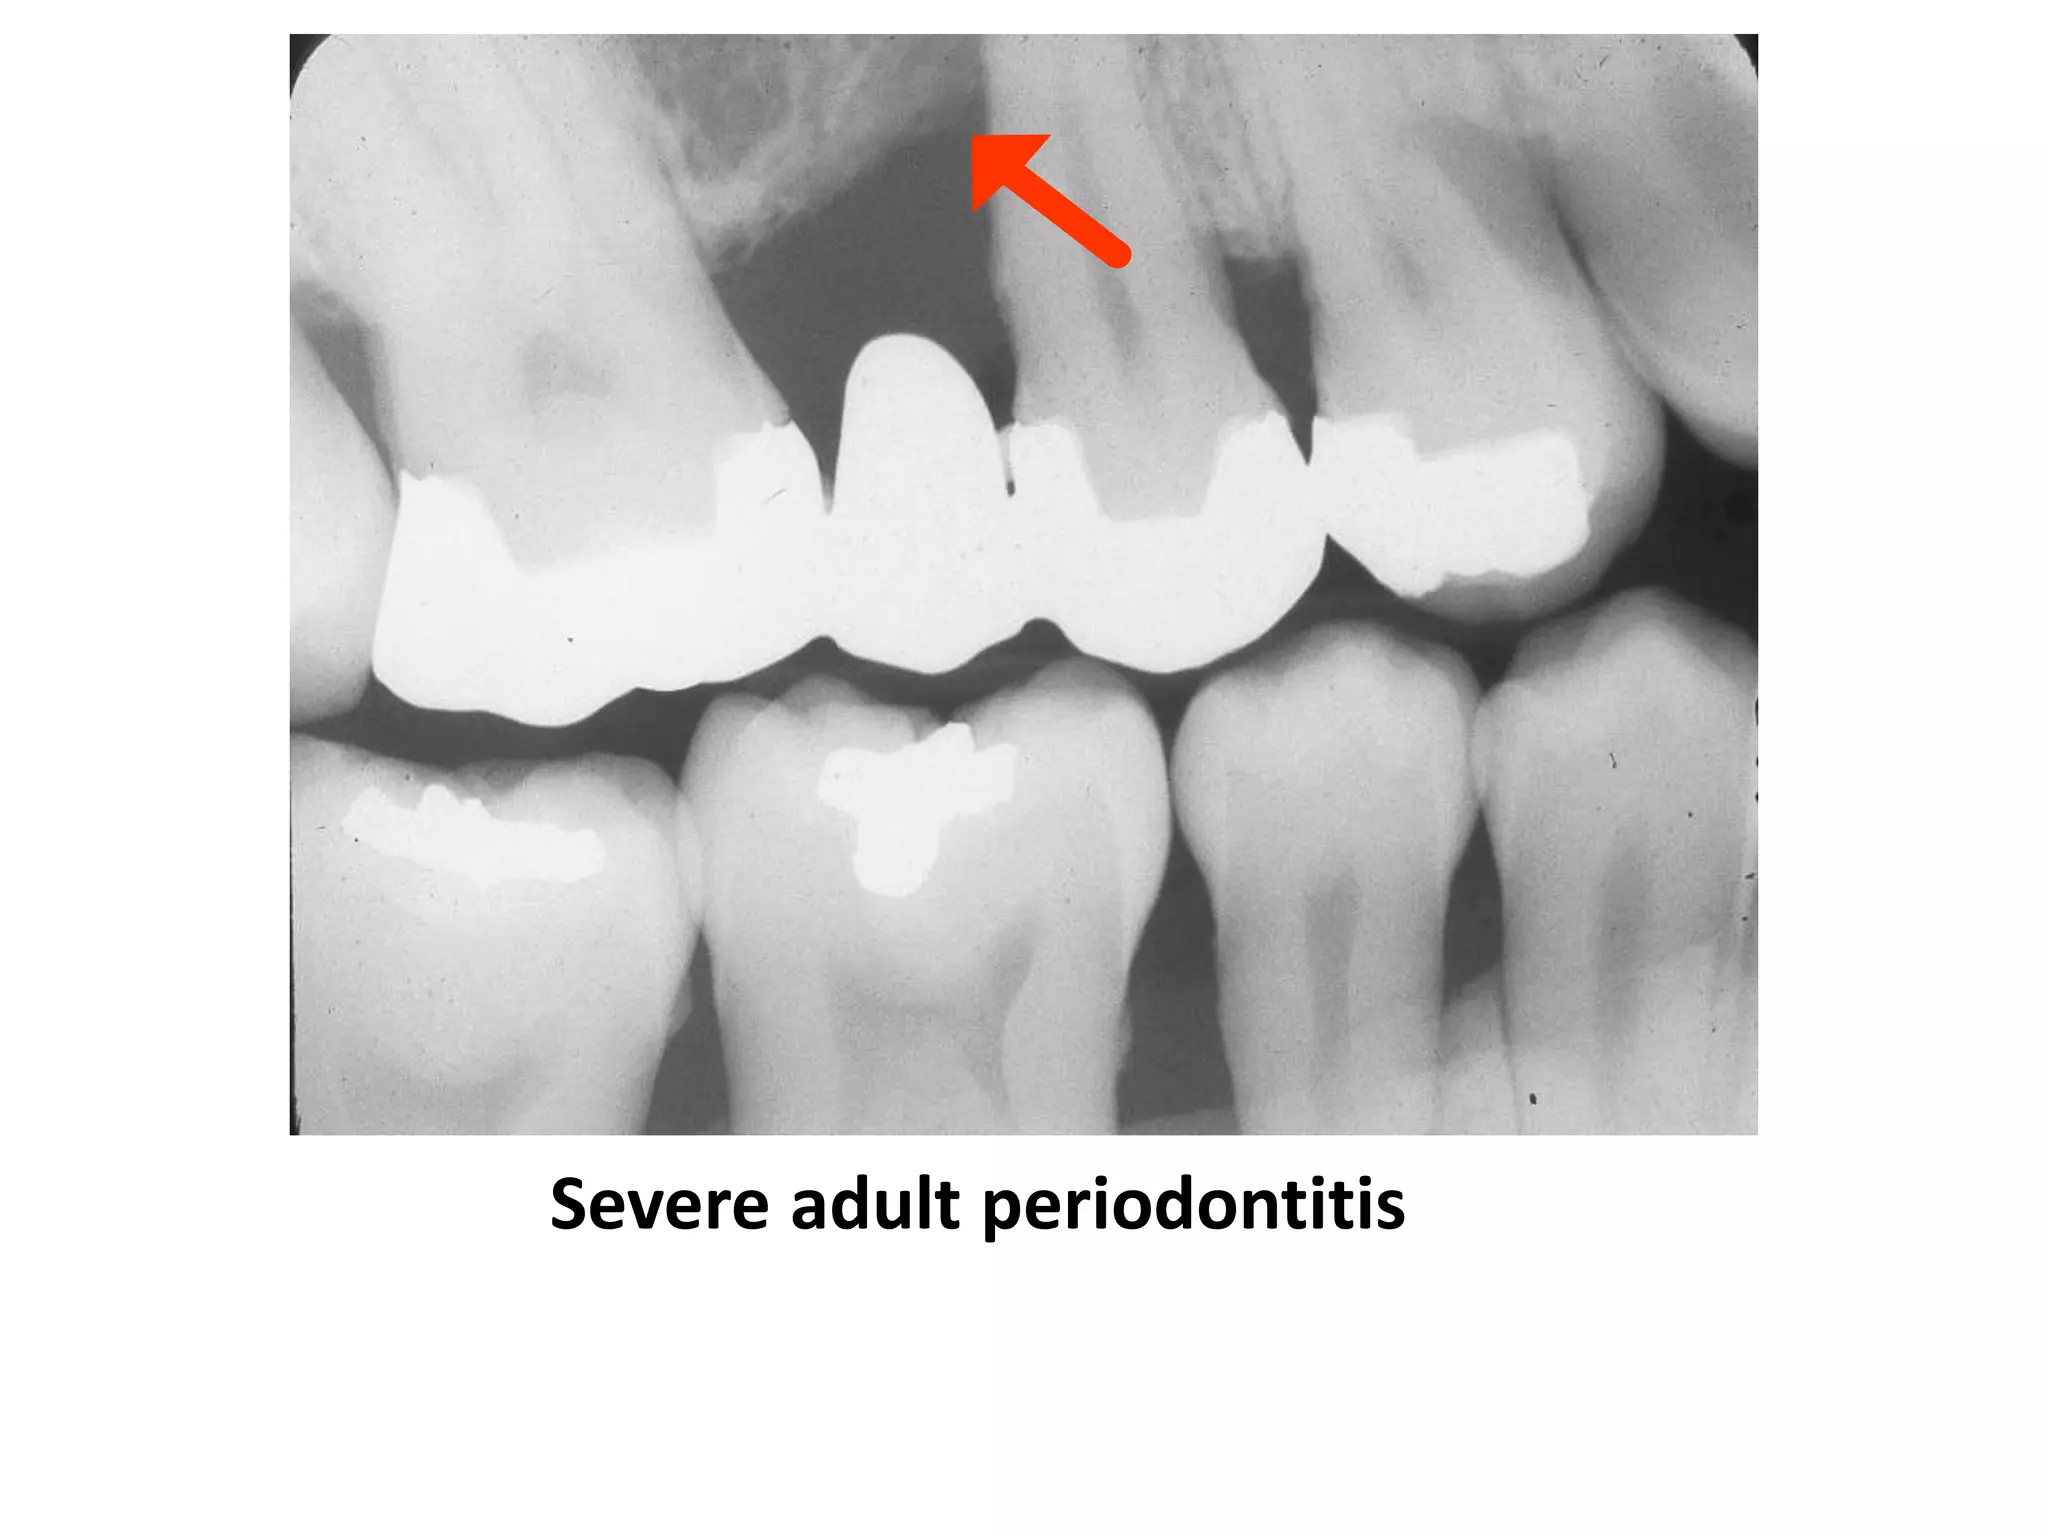

Severe Adult Periodontitis

Tooth mobility

Extensive horizontal bone

loss or vertical osseous

defects

Furcation involvement

Severe adult

periodontitis